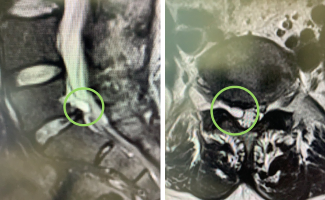

Nice reminder that not all nerve root compression is discogenic in nature. This 43 year old man presented with nerve root symptoms caused by a facet joint cyst that need aspiration. Symptoms improved immediately!